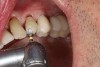

A 71-year-old man presented with acute pain in tooth No. 29 that was spontaneous, unresponsive to vitality testing, and sensitive to percussion. He was referred to an endodontist for treatment of acute apical periodontitis due to the non-vitality of the nerve. Because of the multiple restorations and lingual decay of the tooth, enamel and dentin were compromised, causing the tooth to be biomechanically at high risk and requiring an eventual post-and-core and crown (Figure 1 and Figure 2). Endodontic care included nonsurgical intracanal therapy and creating room for a post space.

Fig 1. Multiple restorations decrease enamel and dentin strength, requiring full-coverage enhancement.

Figure 1

Fig 2. Preoperative view of tooth to be restored shows defective Class 5 restoration that unfortunately was mirrored on the lingual gingival margin.

Figure 2

Fig 4. Depth cutting allows precision reduction to avoid overreduction and compromise of restorative strength.

Figure 4